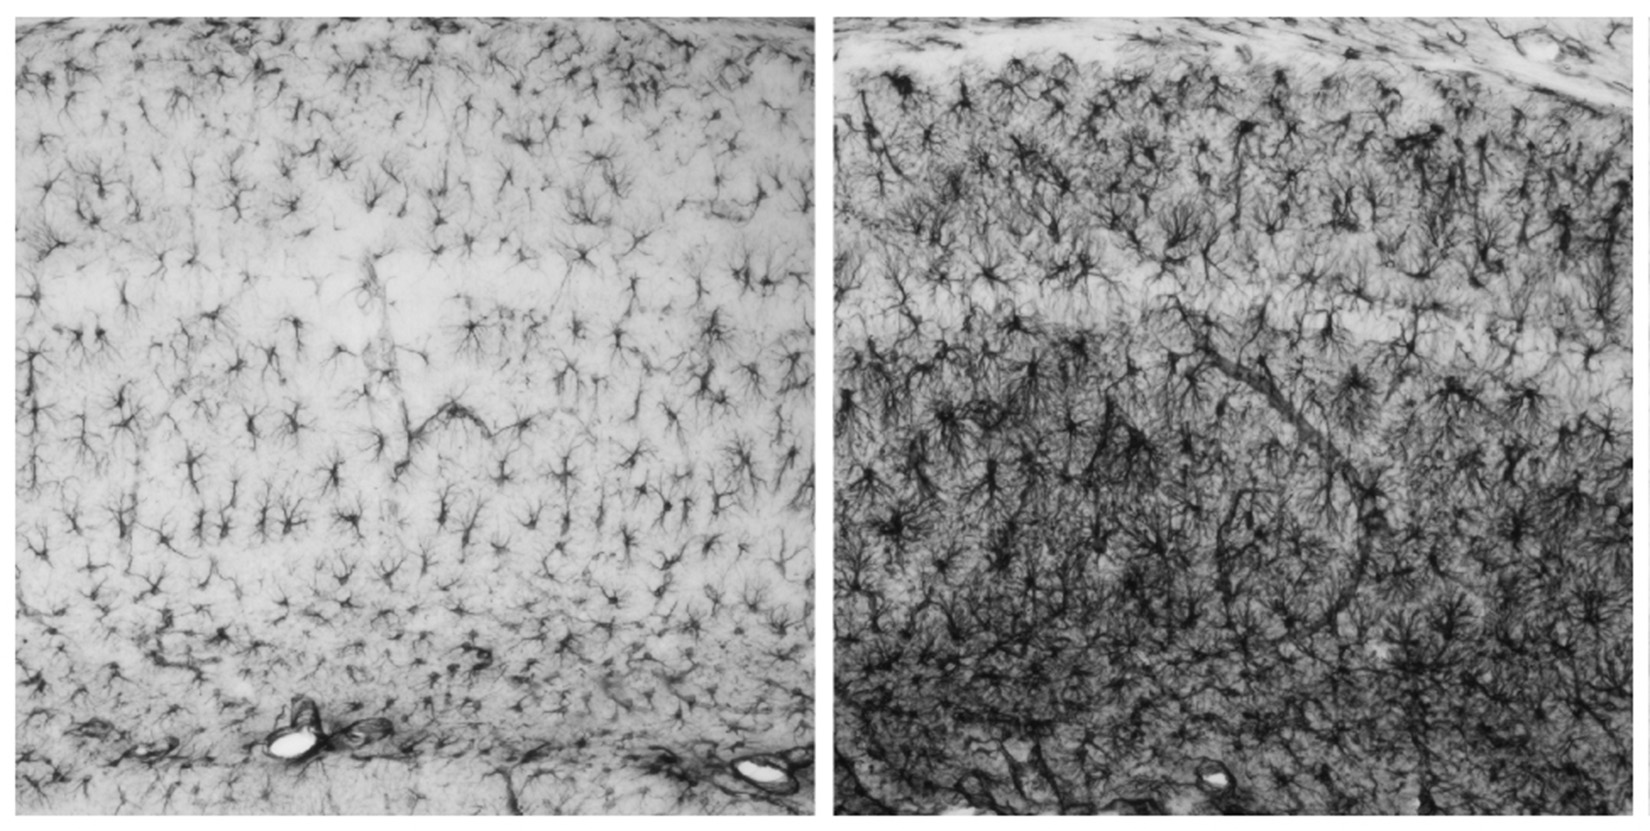

“És la primera epilèpsia de la que coneixem les bases moleculars”, explica Guinovart. Es transmet de forma hereditària a través de pares portadors de mutacions en un dels dos gens relacionats amb la malaltia. Aquests gens són la laforina (anomenada així en honor al Dr. Lafora, neuròleg espanyol descobridor de la malaltia) i la malina (del terme francès le grand mal usat per referir-se a les epilèpsies). La malaltia es caracteritza per l’acumulació a les neurones d’uns depòsits anormals anomenats “cossos de Lafora”.

Guinovart i el seu equip, especialistes en el metabolisme del glicogen, van demostrar al 2007 en un article a Nature Neuroscience que mutacions en qualsevol d’aquests dos gens provoquen l’acumulació de glicogen –cadenes de sucre- a les neurones, cosa que és tòxica per elles i precipita la seva mort cel·lular. Així mateix, van demostrar en ratolins que bloquejant la síntesi de glicogen a les neurones, la malaltia no es desencadena, i van identificar d’aquesta manera un possible tractament per a Lafora.